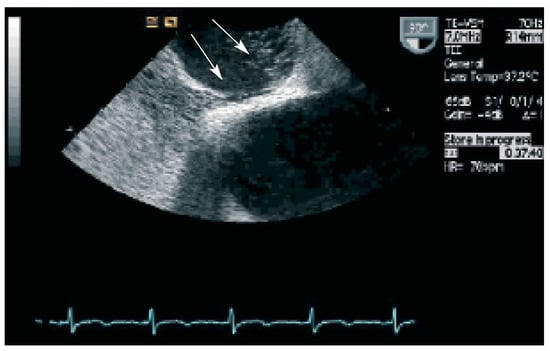

Verglichen mit einer altersentsprechenden Kontrollbevölkerung ist bei Personen mit grossem Vorhofseptumaneurysma, OFO und Nachweis von spontanem Luftbläschenübertritt im Echokardiogramm (Abb. 1) das Risiko für ein kryptogenes zerebrovaskuläres Ereignis auf das 5bis 16fache erhöht, sogenannte «high risk features» [7]. Gelegentlich werden diese Zusammenhänge jedoch auch in Frage gestellt [8]. Einige Autoren verneinen explizit einen Zusammenhang zwischen zerebrovaskulären Ereignissen und einem OFO [9]. Die Indikation zum perkutanen Verschluss des OFO wird unterschiedlich gehandhabt. Diese reicht vom dogma tischen «every hole has to be closed» bis zur konsequenten Zurückhaltung auch nach mehreren zerebrovaskulären Ereignissen bei fehlender andersweitiger Ursache.

Abbildung 1. Spontaner Kontrastmittel-Übertritt durch das OFO in den linken Vorhof (Pfeile).